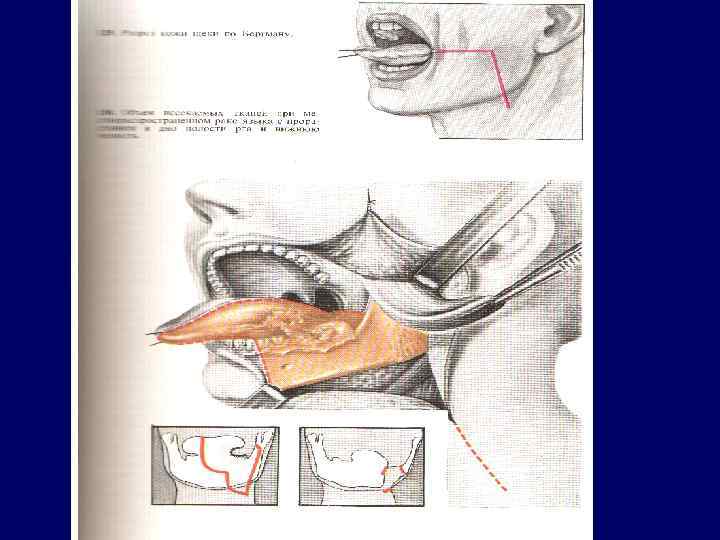

Рак языка 60 -70% - с/3 боковой поверхности и более 20% в корне языка; Плоскоклеточный рак, в корне лимфоэпителиома, аденокарцинома – 1, 5 -3% из малых слюнных желез в языке. Течение рака неблагоприятное, для прогноза имеет значение локализация опухоли. Рак корня языка (III злокачественности плоскоклеточный и лимфоэпителиома) обладает быстрым ростом, дает ранние и частые метастазы в регионарные глубокие шейные лимфоузлы. Рак в среднем и переднем отделах языка (I и II степень) метастазирует в подбородочные, нижнечелюстные и глубокие шейные лимфоузлы

Рак языка 60 -70% - с/3 боковой поверхности и более 20% в корне языка; Плоскоклеточный рак, в корне лимфоэпителиома, аденокарцинома – 1, 5 -3% из малых слюнных желез в языке. Течение рака неблагоприятное, для прогноза имеет значение локализация опухоли. Рак корня языка (III злокачественности плоскоклеточный и лимфоэпителиома) обладает быстрым ростом, дает ранние и частые метастазы в регионарные глубокие шейные лимфоузлы. Рак в среднем и переднем отделах языка (I и II степень) метастазирует в подбородочные, нижнечелюстные и глубокие шейные лимфоузлы

Рак языка (экзофитная форма)

Рак языка (экзофитная форма)

Рак боковой поверхности языка (язвенная форма)

Рак боковой поверхности языка (язвенная форма)